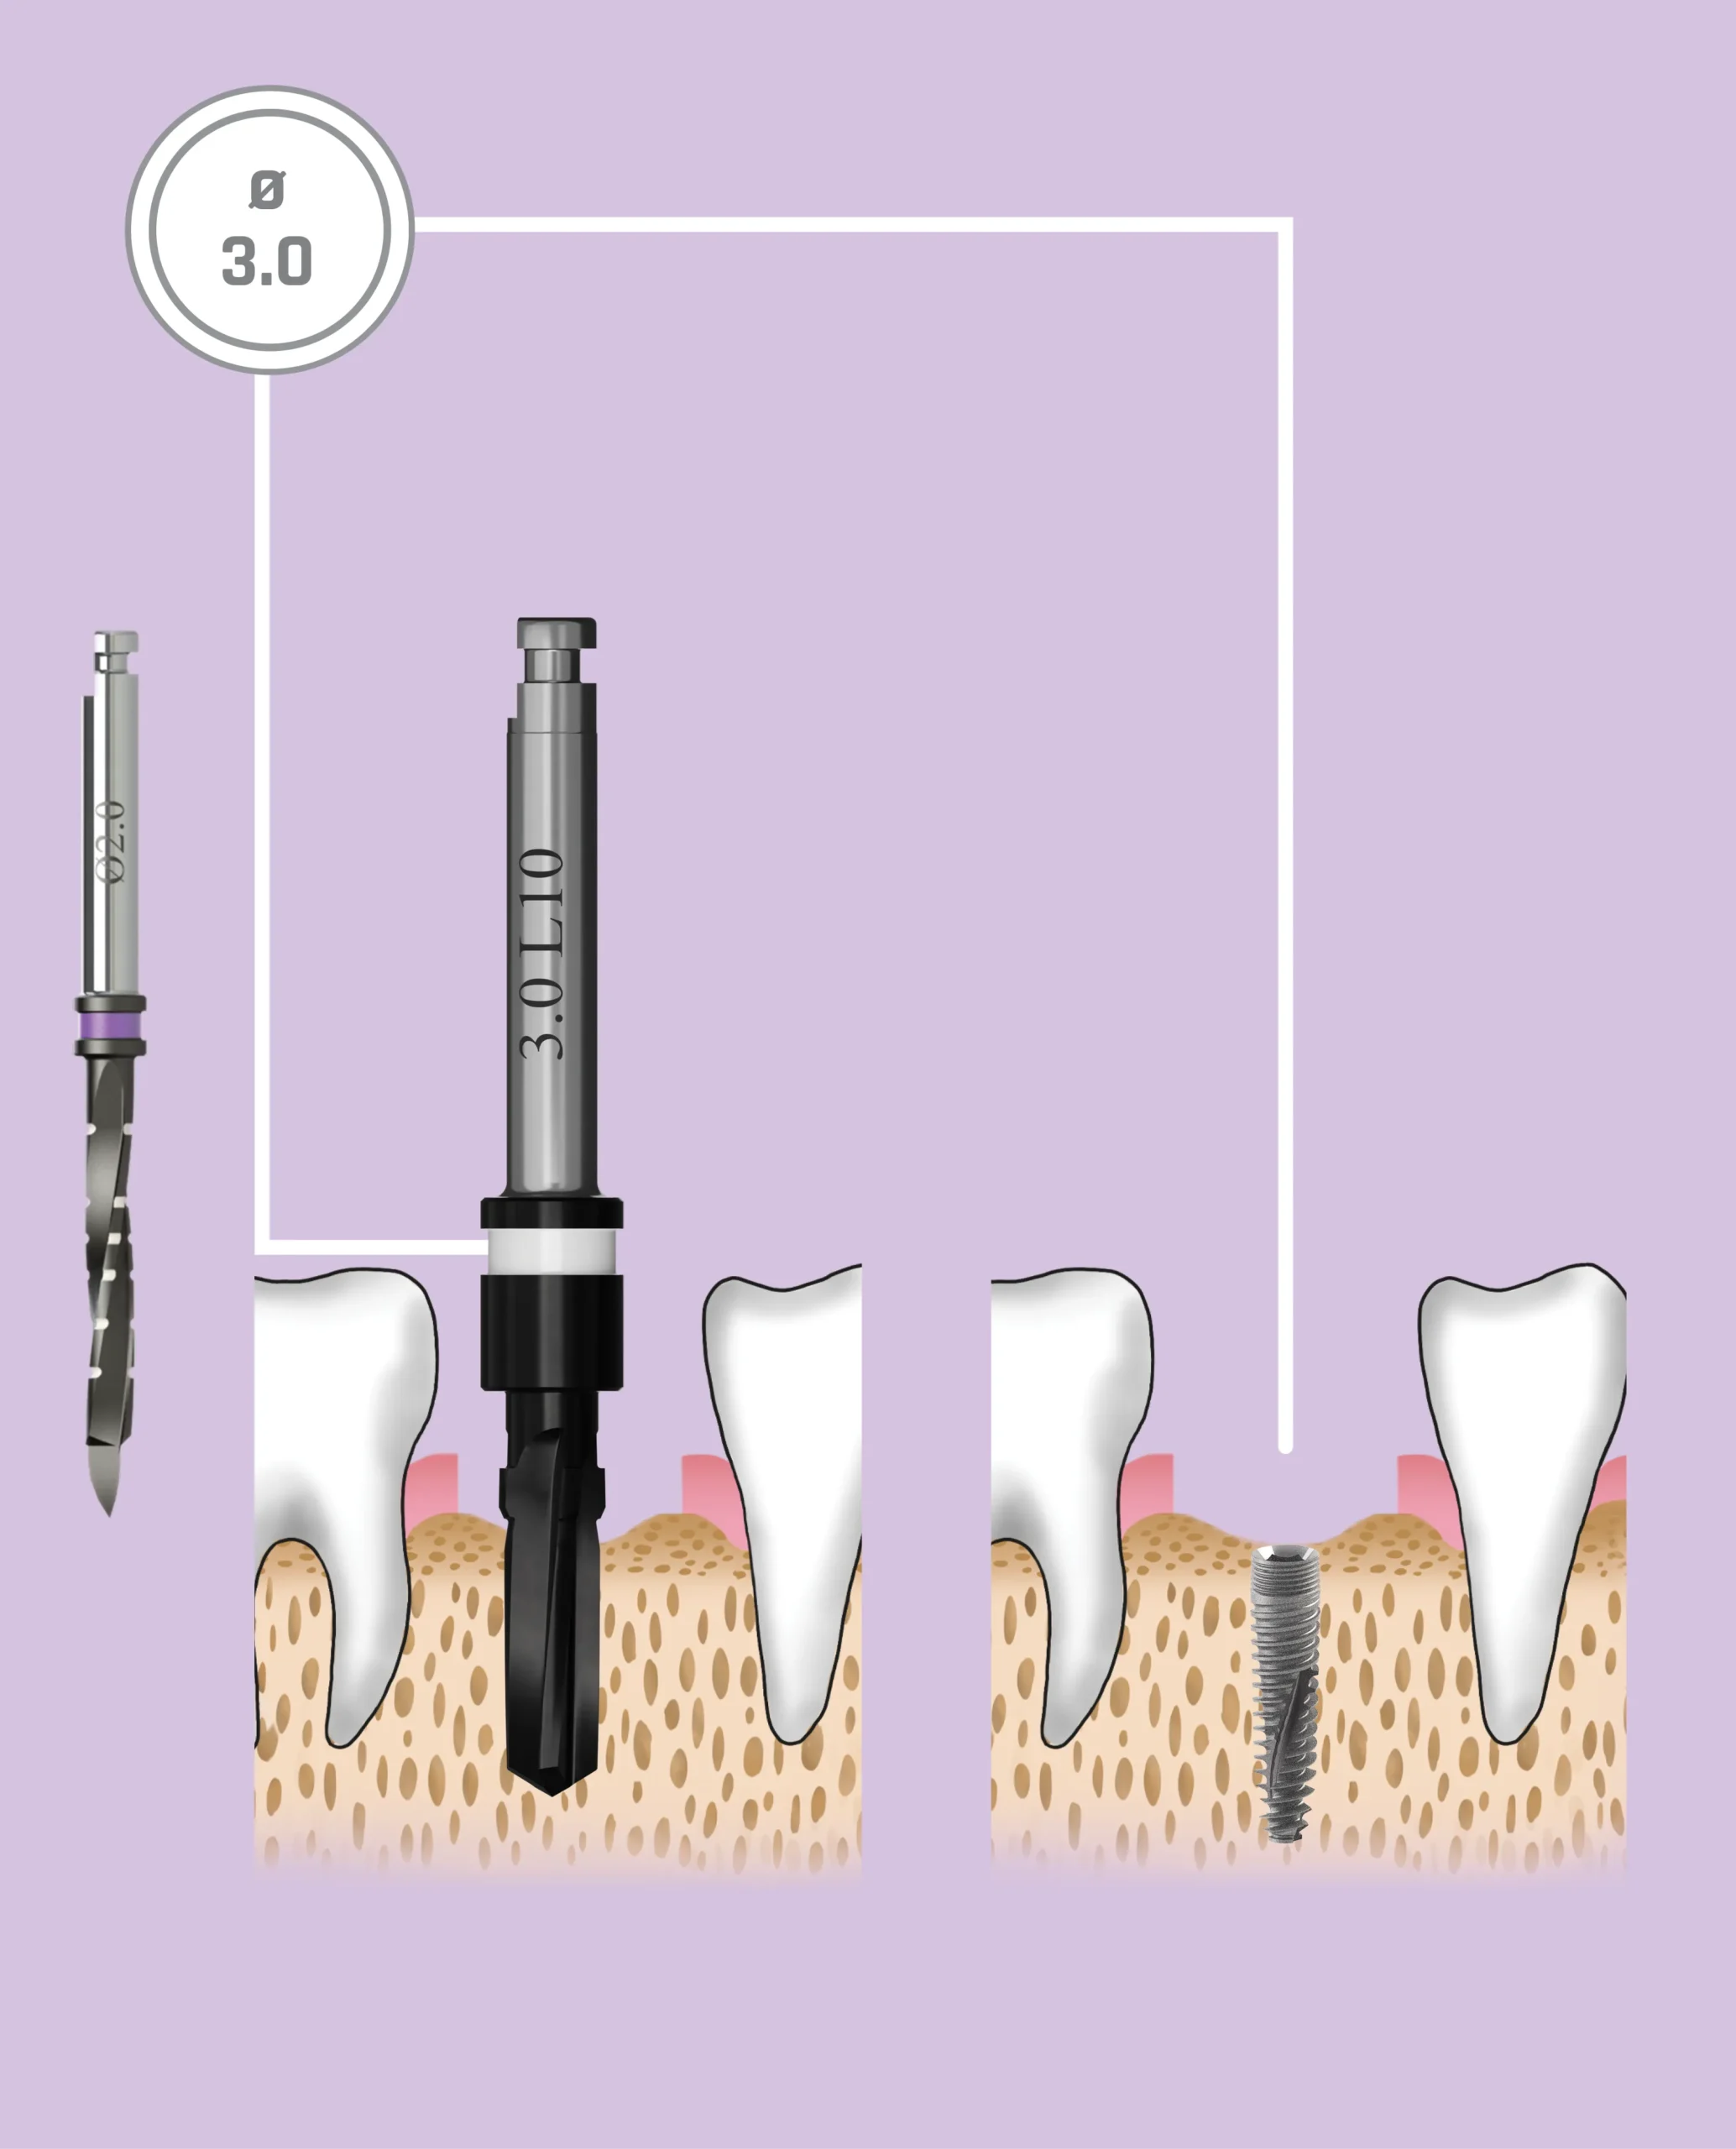

Quy trình mũi khoan

Nên sử dụng mũi khoan mồi 2.0 mm cho tất cả các đường kính implant. Các implant có đường kính 3.0 mm và 3.3 mm (Dòng Hẹp – Narrow Line) cùng với implant đường kính 3.75 mm (Dòng Tiêu Chuẩn – Standard Platform) nên được đặt ngang mức đỉnh xương. Các implant đường kính 4.2 mm, 5.0 mm và 6.0 mm (Dòng Tiêu Chuẩn – Standard Platform) có thể được đặt dưới mức đỉnh xương

| Đường kính Implant | 3.0 mm | 3.3 mm | |

|---|---|---|---|

| Mã màu | white | red | |

| Tổng số mũi khoan | 2 | 3 | |

| Mũi khoan cuối cùng | 2.5 mm | 2.8 mm | |

| Mũi khoan lớn nhất phù hợp với đường kính Implant | 2.5 mm | 2.8 mm | |